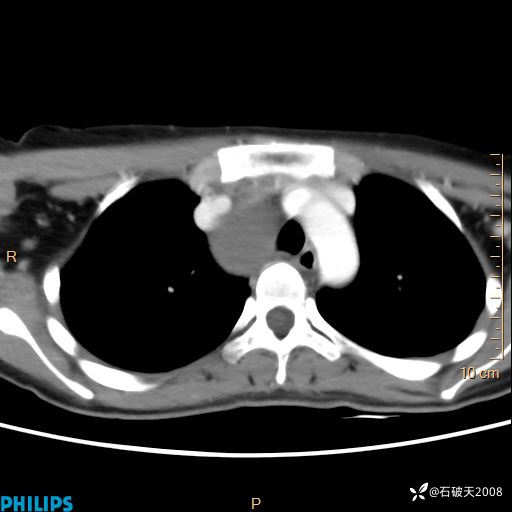

影像诊断要密切结合临床,真的很有必要(病理已公布)

女 21岁 主 诉:发现右侧颈部肿物18年余。

现病史:18年余前患者无明显诱因发现颈部偏右侧有一肿物,具体大小不明确,咳嗽、憋气时肿物增大,局部无疼痛,无吞咽不适,无胸闷及呼吸困难,至当地医院检查考虑良性病变(具体不详)并未做特殊处理,现患者自觉肿物随年龄增长而进一步变大,今日至我院行颈部CT平扫+增强提示:1.右侧颈根部、锁骨上窝及纵隔内异常密度影,考虑良性病变,淋巴管瘤?囊肿?请结合临床。2.双侧颈部小淋巴结。建议结合临床及其他相关检查。现为行进一步治疗,门诊以“颈部局部肿物”为诊断收住我科,发病来患者神志清,精神可,饮食睡眠可,大小便正常,体重无下降。

静脉期